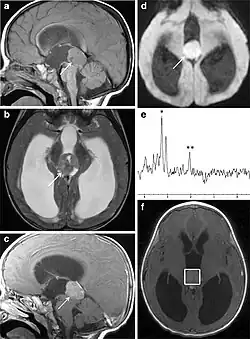

Pineoblastoma on brain imaging

Several imaging methods can be used to diagnose pineoblastoma. Initially, urgent CTs are recommended, followed by MR imaging.[13] CT will show large, multilobulated masses with heterogenous contrast enhancement and peripheral calcification of the pineal gland.[4][3] On MRI, pineoblastomas again appear as masses with heterogenous enhancement. They often appear hypo- to isointense on T1 and slightly hyperintense on T2-weighted images. Some areas of necrosis or hemorrhage may be seen as well. PET-CT has also been used in diagnosis, and shows increased uptake of fludeoxyglucose with pineoblastomas compared to other pineal masses.